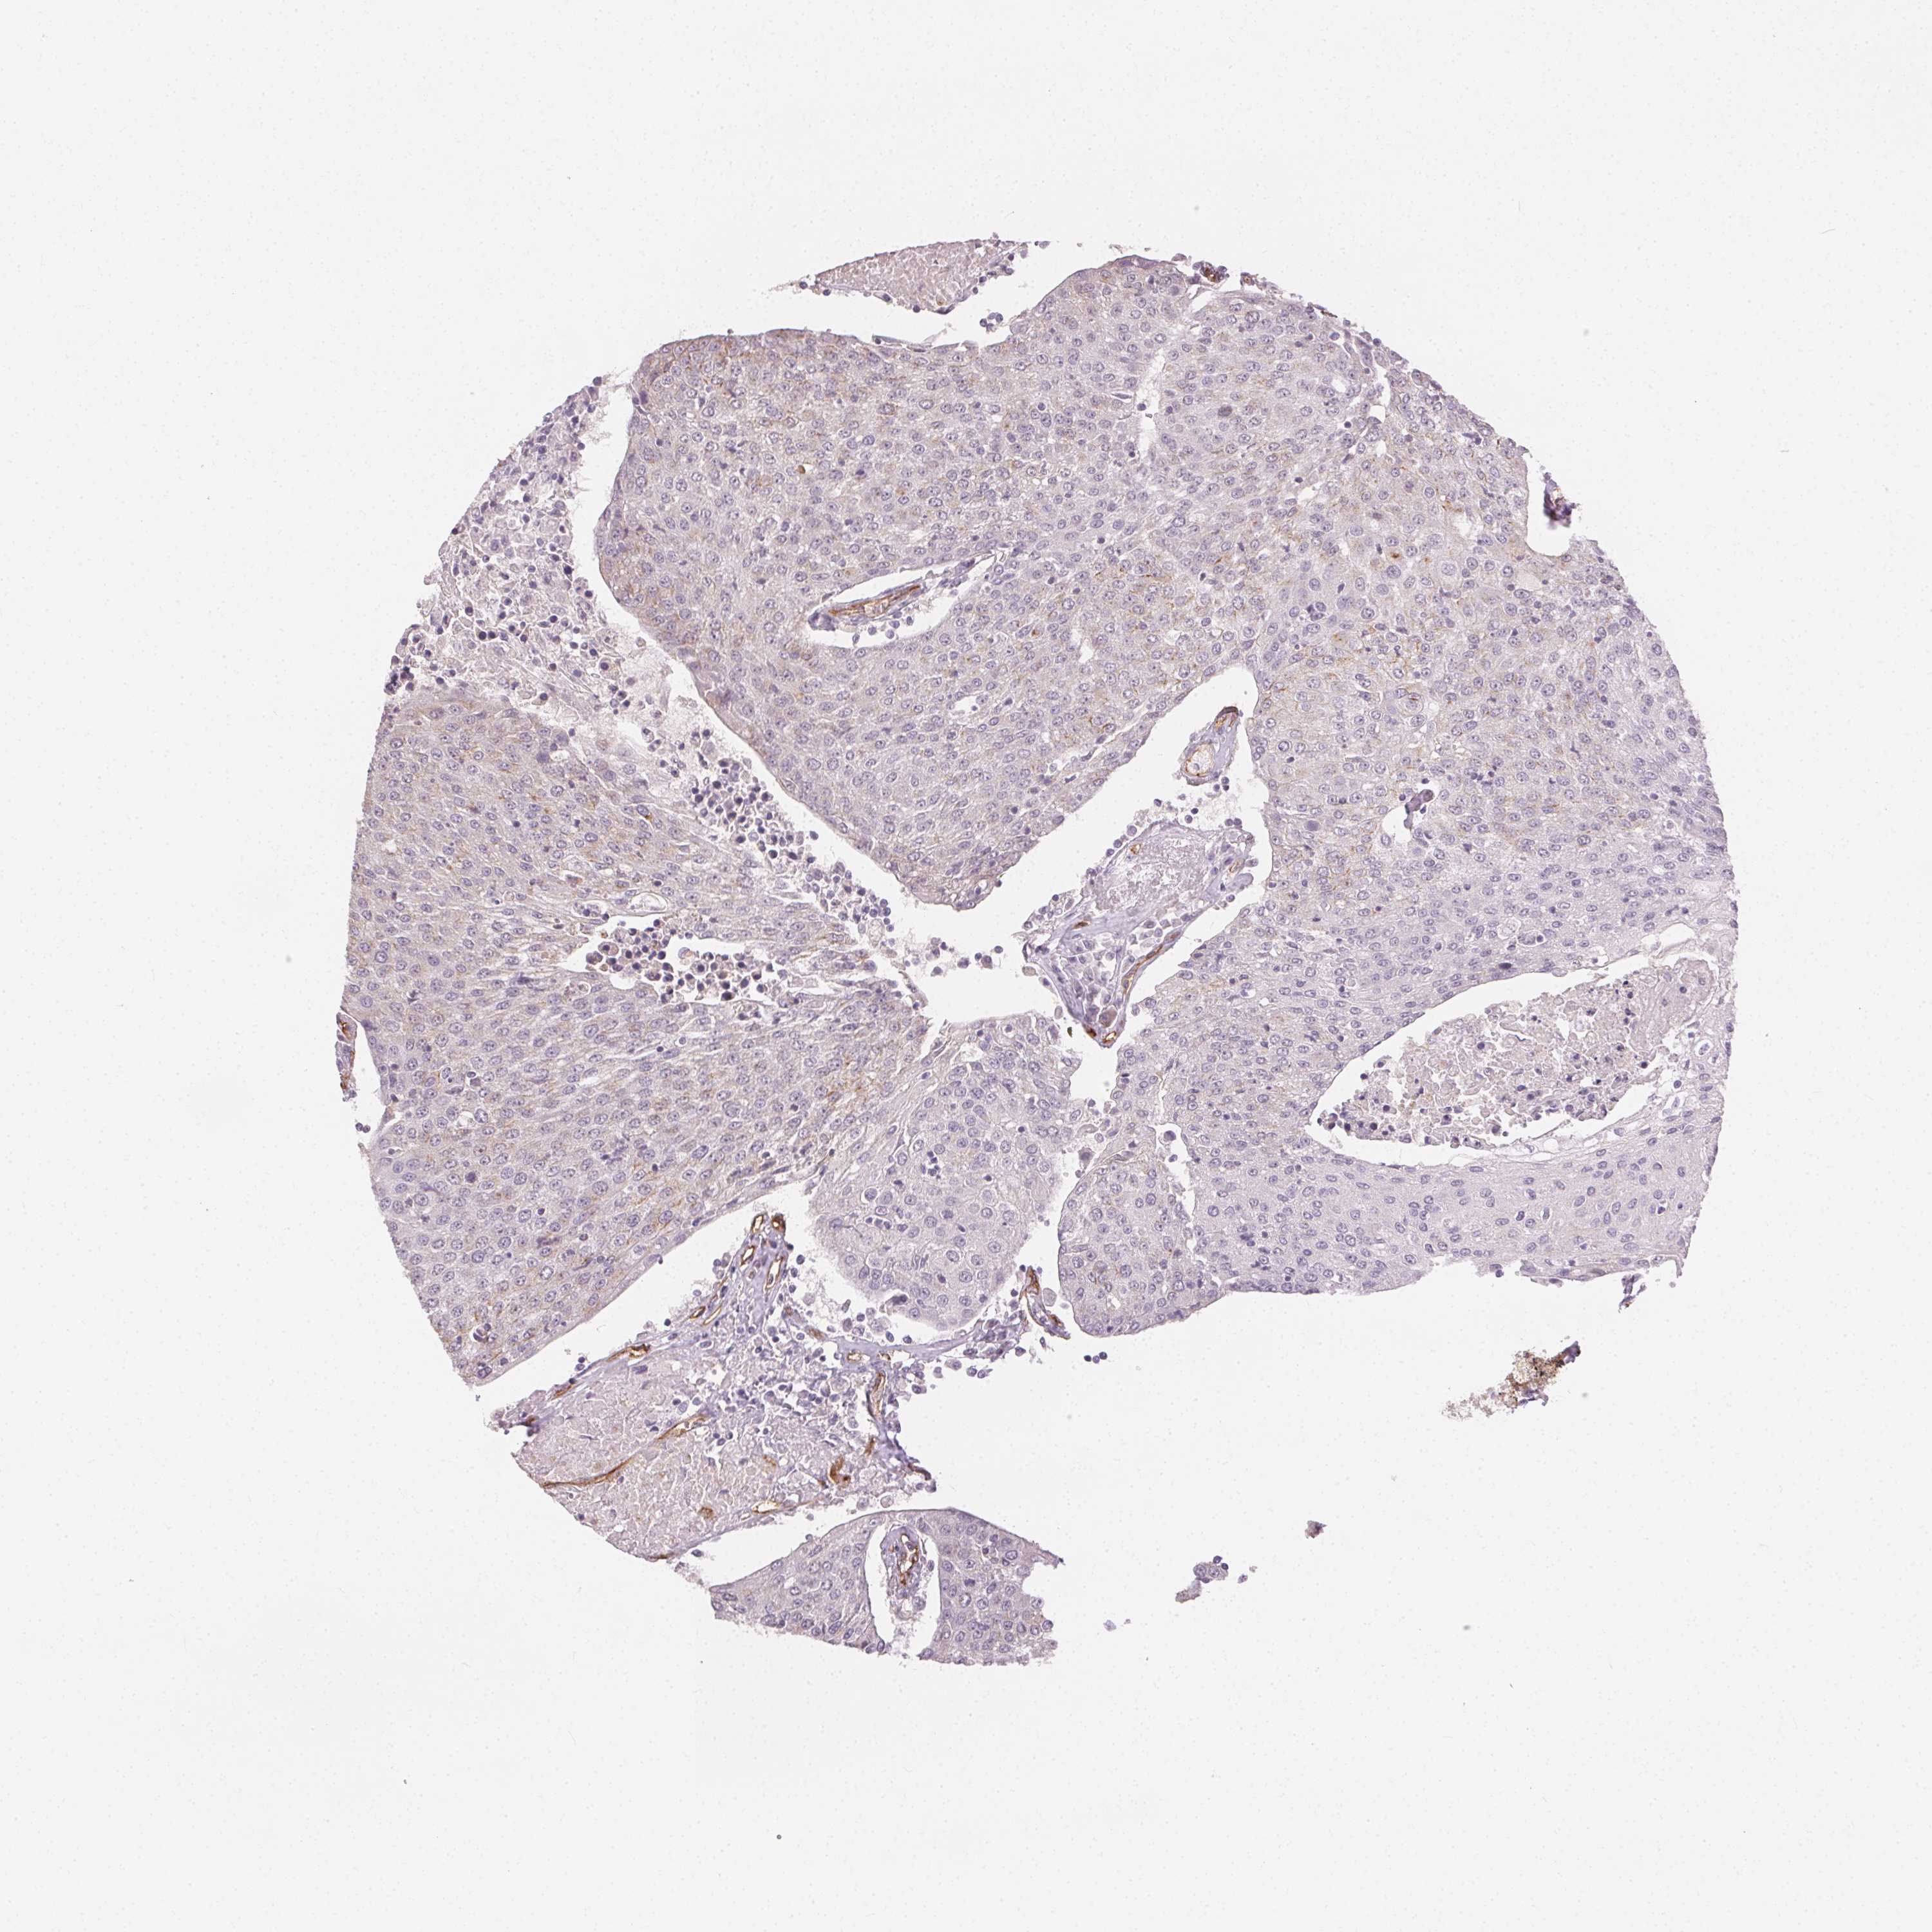

UROTHELIAL CANCER - Protein expressioni

A mouse-over function shows sample information and annotation data. Click on an image to view it in a full screen mode. Samples can be filtered based on level of antibody staining by selecting one or several of the following categories: high, medium, low and not detected. The assay and annotation is described here.

Note that samples used for immunohistochemistry by the Human Protein Atlas do not correspond to samples in the TCGA dataset.

Antibody stainingi

Antibody staining in the annotated cell types in the current human tissue is reported as not detected, low, medium, or high, based on conventional immunohistochemistry profiling in selected tissues. This score is based on the combination of the staining intensity and fraction of stained cells.

Each image is clickable and will lead to virtual microscopy that enables deeper exploration of all samples and also displays staining intensity scores, fraction scores and subcellular localization as well as patient and tissue information for each sample.

HPA002110

HPA045507

CAB016169

CAB062558

CAB068219

CAB068220

Urothelial carcinoma, High grade

Urothelial carcinoma, NOS

Urothelial carcinoma, Low grade